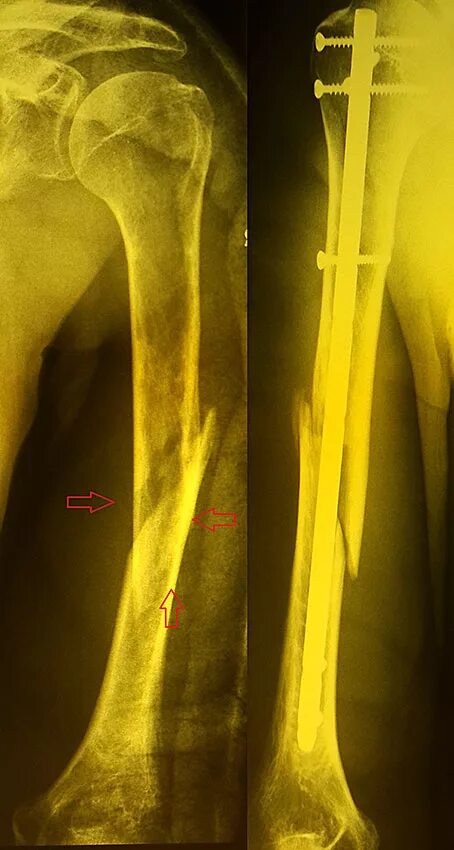

Оскольчатый перелом плеча со смещением